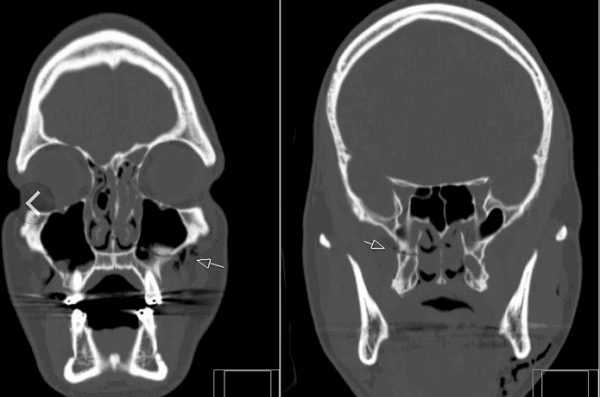

Безусловным преимуществом компьютерной томографии является возможность визуализации повреждения дистального межберцового сочленения. Количественная оценка диастаза рентгеновской щели между берцовыми костями и ротации малоберцовой кости позволяет выявить еще одну возможную причину нестабильности голеностопного сустава и болевого синдрома (рис. 3).

Компьютерная томография — хороший инструмент в оценке эффективности проводимого консервативного или оперативного лечения. Даже несмотря на множественные линейные артефакты от металлических фиксирующих конструкций, практически всегда возможно определить правильность сопоставления отломков, устранение патологического диастаза между отломками или костями (рис. 3).